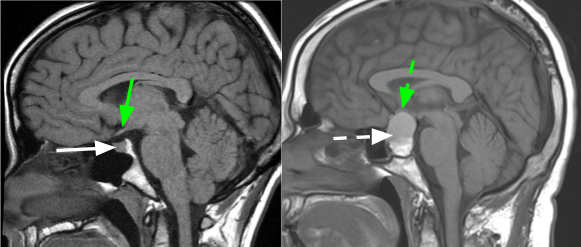

垂体,是我们大脑中一个小小小东西,它虽小,但却绝对不弱,小小的身体有大大的能量。它可以分泌多种内分泌激素,参与正常生活活动,凭着过硬的实力,它走上C位--人体“内分泌腺”之首。而垂体瘤就是来源于垂体本身的一种肿瘤。

这类垂体瘤不分泌激素,一般情况下无明显症状,但随着肿瘤体积的增大,肿瘤向上生长可压迫视神经,引起视力下降,视野缺损,一般老年人极易被误诊为老花眼、白内障等眼病,但经眼科治疗后症状一般无改善;若是肿瘤向两侧生长可压迫海绵窦,引起眼球运动障碍,眼睑下垂等,除此之外,还可能有头痛、记忆力下降、反应迟钝等症状。